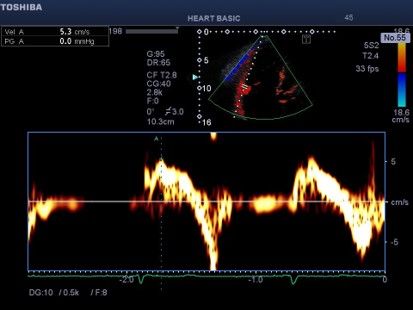

Εικόνα 2 . Συνεχές Doppler δια της τριγλώχινας . Το σχήμα του σήματος της

τριγλωχινικής ανεπάρκειας είναι τριγωνικό λόγω εξίσωσης πιέσεων μεταξύ δεξιάς κοιλίας και δεξιού κόλπου και θυμίζει αορτική ροή (αορτοποίηση).

Υπάρχει βραχεία άνοδος της ταχύτητας ροής (επηρεασμένο dp /

ενδεικτικό συστολικής δυσλειτουργίας της δεξιάς κοιλίας. Η προς τα

πρόσω ροή (κύμα Ε) της τριγλώχινας έχει σχετικά υψηλή ταχύτητα παρά τη

διάταση του δακτυλίου εύρημα σχετιζόμενο με την αυξημένη ροή.